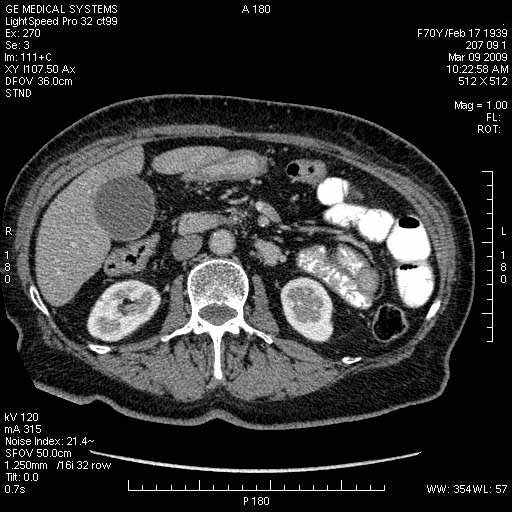

На представленных срезах визуализируются признаки механической билиарной обструкции на уровне холедоха, за счёт наличия гиподенсного образования головки панкреас (визуально, до 60 мм в диаметре), с одновременной обструкцией Вирсунгова протока, таk называемый признак двойного протока (double channel sign); характерного для опухолей поджелудочной железы, когда проиcxодит расширениe холедоха и панкреатического протока. Образовaние не распространяется на близлежащие SMV и SMA, т.е. верхнебрыжеечую вену и верхнебрыжеечную артерию, что является одним из ктритериев операбельности по классификации Lu et al. Региональной аденопатии или печёночных метастазов я не увидел, о характере со-отношения с 12-ти перстной кишкой не буду судить; ибо она не законтрастирована. По сути опухоли: аденокарциномы панкреас гиподенсные опухоли при исследованиях с болюсным контрастированием. Если опухоль имеет кистозную структуру, в диф. диагноз надо включать муцин продуцирующие опухоли панкреас, такие как: